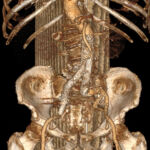

Ανεύρυσμα κοιλιακής αορτής-Ανοιχτή Αποκατάσταση

Η ανοιχτή αποκατάσταση ανευρύσματος κοιλιακής αορτής είναι χειρουργική επέμβαση κατά την οποία το παθολογικά διατεταμένο τμήμα της αορτής αντικαθίσταται με συνθετικό αγγειακό μόσχευμα για την αποκατάσταση της φυσιολογικής ροής του αίματος.